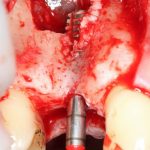

Прежде, чем приступить к аугментации (пластике) лунок зубов, мы подготовили лунки для имплантатов. В таких клинических случаях нет необходимости в использовании шаблона. Вместо этого, мы применяем общепринятые правила позиционирования и соблюдаем рекомендации производителя по хирургическому протоколу:

В процессе ирригации лунки промываются, что позволило нам еще раз подтвердить ранее сделанные выводы. С помощью аналогов имплантатов, входящих в хирургический набор Xive, мы проверили возможность стабилизации имплантатов в будущих лунках. Исходя из правил подбора и позиционирования имплантатов (я очень рекомендую почитать об этом здесь>>) мы остановились на Xive S диаметром 3,4 мм и длиной 13 мм.

Подготовка двух лунок для имплантатов занимает около 10 минут.